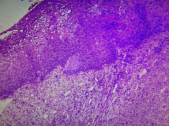

子宮頸上皮內瘤變

子宮頸上皮內瘤變(CIN)是指子宮頸上皮被不同程度異型性的細胞所取代。表現為細胞大小形態不一,核增大深染,核質比例增大,核分裂象增多,細胞極性紊亂。病變由基底層逐漸向表層發展。

根據其病變程度不同分為三級:Ⅰ級,異型細胞局限于上皮的下1/3,Ⅱ級,異型細胞累及上皮層下1/3至2/3,Ⅲ級,增生的異型細胞超過全層的2/3,包含原位癌。子宮原位癌是指異型增生的細胞累及子宮頸黏膜上皮全層,但病變局限于上皮層內,未突破基底膜。原位癌的細胞可由表面沿基底膜通過宮頸腺口蔓延至子宮頸腺體內,取代部分或全部腺上皮,但仍未突破腺體的基底膜,稱為原位癌累及腺體,仍然屬于原位癌的范疇。

CINⅠ級 CINⅡ級 CINⅢ級